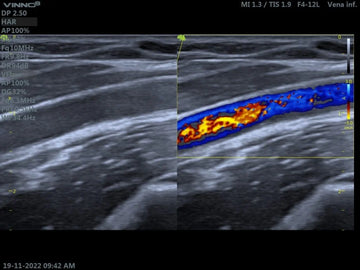

La ecografía veterinaria abdominal es una herramienta esencial en la medicina, permitiendo a los especialistas observar con claridad los órganos internos de nuestros animales sin necesidad de métodos invasivos. Esta imagen ecográfica, obtenida mediante un equipo VINNO VET, es un ejemplo de cómo la tecnología avanzada está transformando el diagnóstico veterinario.

En la medicina veterinaria, las ecografías son fundamentales para identificar diversas condiciones de salud en animales. La imagen mostrada corresponde a una ecografía abdominal que proporciona detalles importantes sobre las estructuras internas del animal. Al igual que en la medicina humana, esta técnica permite a los veterinarios visualizar órganos como los riñones, el hígado, los intestinos y otros órganos abdominales.

En esta ecografía, observamos una estructura abdominal en un plano transversal. Las imágenes como estas permiten estudiar:

La claridad de la imagen es esencial para que el veterinario pueda evaluar si los órganos están en su tamaño normal y si presentan alguna alteración. En la imagen proporcionada, las estructuras observadas parecen indicar un estudio abdominal rutinario, pero su interpretación dependerá del historial clínico del paciente.

El equipo VINNO VET, utilizado para obtener esta imagen, destaca por su precisión y facilidad de uso en clínicas veterinarias. Su tecnología avanzada permite imágenes claras y detalladas, lo que es crucial para el diagnóstico veterinario. Además, su versatilidad hace que sea ideal para pacientes de diferentes tamaños, desde perros y gatos hasta animales exóticos o de granja.